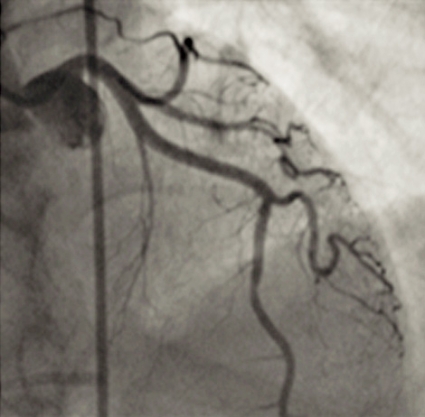

Till vår stora förvåning visade angiografin inga signifikanta stenoser (Figur 2) eller andra uppenbara tecken på akut koronarsyndrom. Flödet i LAD (främre nedåtstigande grenen av vänster koronarartär) var något långsammare än normalt, men för övrigt såg vi inget anmärkningsvärt.